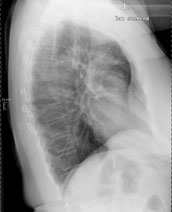

Eine 69-jährige Patientin klagt über einen seit mehr als 4 Wochen anhaltenden Husten mit wenig Auswurf. Die Frage nach Dyspnoe wird verneint. Fieber besteht keines.

Die körperliche Untersuchung ist unergiebig. Der behandelnde Arzt hat aufgrund der Raucheranamnese und des nicht enden wollenden Hustens ein Röntgenbild gemacht:

Thorax seitlich